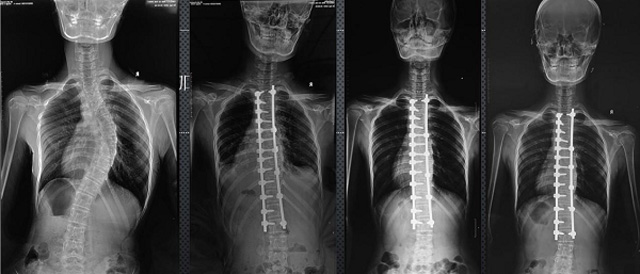

(7)全身拼接功能對(duì)有較大尺寸全脊柱拼接圖接桂成金下股分成幾次拍攝,再經(jīng)過秋件開在骨科開展的全脊柱畸形矯治工作中,雖然CT. MRI也能獲取全脊柱影像,接圖像,以便于長(zhǎng)度、角度、力線等測(cè)量和察脊柱在重力情況下但不能進(jìn)行立位檢查,無(wú)法觀全景觀察。全身拼接功能是高等級(jí)DR攝取患者立位全下的功能狀態(tài)圖像,因此采用動(dòng)態(tài)醫(yī)院特別看重的動(dòng)態(tài)DR功能之一。注:圖中Cobb脊柱正側(cè)位圖像是首選的檢查方法角度的大小是反映側(cè)彎嚴(yán)重程度的一個(gè)標(biāo)準(zhǔn)。